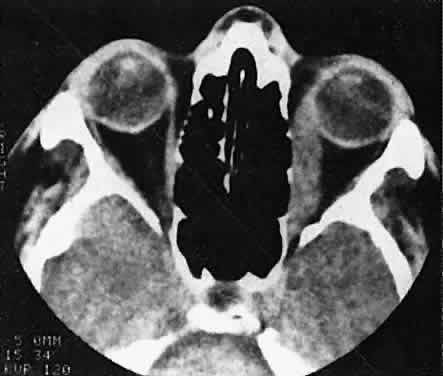

Orbital myositis may represent a greater proportion of cases of IIPT in childhood than in adulthood, and involvement of multiple extraocular muscles may occur more frequently in children than inadults. In orbital myositis, early diplopia and increased discomfort with attempted eye movement are typical symptoms. CT may show enlargement of one or more extraocular muscles in one or both orbits (Figs. 21 and 22). When a single muscle is involved, the specter of a primary or metastatic neoplasm within the muscle may be raised. However, external inflammatory signs, considerable pain and limited motility, and an explosive onset of symptoms within 24 hours all suggest orbital myositis. The uniform enlargement of the muscle, including its tendinous insertion (see Fig. 22), also helps distinguish the process from a neoplasm, which might be expected to produce a more focal, globular expansion. Echography may support the diagnosis of inflammation by showing edema in the episcleral space as a relative sonolucency between the scleral and orbital fat echoes (Fig. 23). Its CT counterpart is an increase in the radiodensity and thickness of the ocular tunica.

Fig. 21. A. This 16-year-old boy had acute onset of bilateral proptosis, pain, diplopia, chemosis, and conjunctival injection. B. Bilateral enlargement of the superior and medial rectus and inferior oblique muscles. Other sections showed similar involvement of other extraocular muscles.

Fig. 22. The uniform enlargement of the left medial rectus muscle, including its tendinous insertion, is characteristic of orbital myositis.